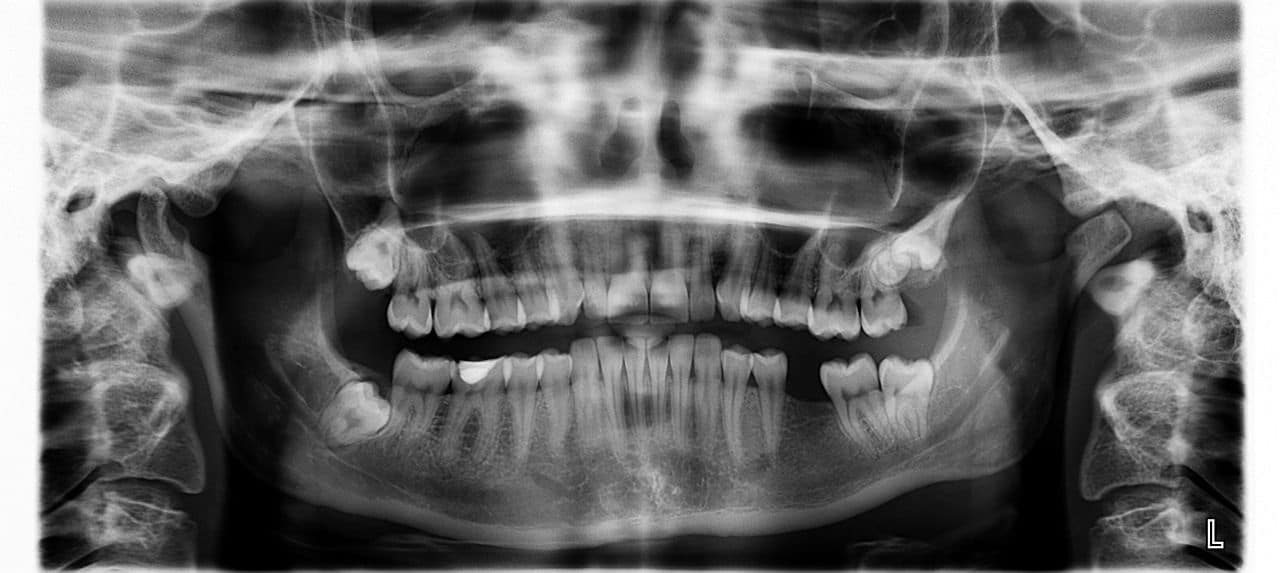

El camino hacia un implante dental comienza con una evaluación exhaustiva por parte del odontólogo o cirujano dental. En esta etapa, se realizan los siguientes pasos:

- Historia clínica: Se revisan antecedentes médicos para identificar posibles riesgos o contraindicaciones.

- Exámenes de diagnóstico: Radiografías y tomografías computarizadas permiten evaluar la calidad y cantidad del hueso disponible.

- Planificación personalizada: Se diseña un plan de tratamiento adaptado a las necesidades específicas del paciente, incluyendo la selección del tipo de implante y la ubicación exacta.

Esta etapa es crucial, ya que un diagnóstico adecuado asegura que el implante se colocará en condiciones óptimas.